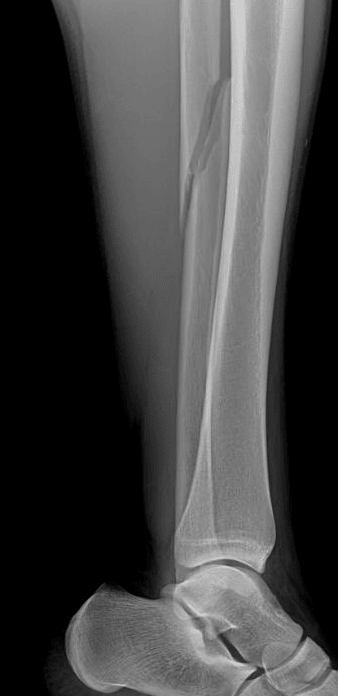

Tibia/fibula radiograph in this patient shows a proximal fibular fracture consistent with a Maisonneuve fracture